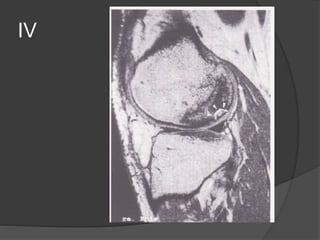

Osteocondritis disecante

 lesión osteocondral originada por traumatismo (50%)

 Mas frecuente niños y adolescentes, en los que el cartílago

articular es más resistente que el hueso subcondral.

 1 y 2 no hay

cambios

artroscópicos

II

IV